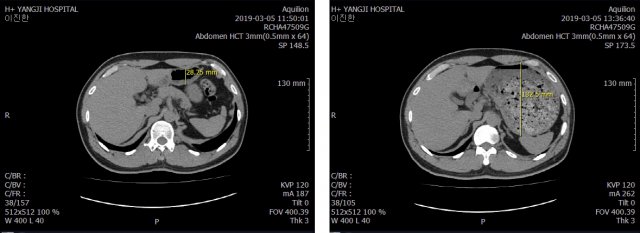

식사 전(왼쪽), 후 (오른쪽) CT 사진초밥 5인분을 먹은 뒤 신체 변화를 살폈다. 몸무게는 1시간여 만에 1.3㎏나 늘었다. 체질량지수는 24.2로 0.5가 증가했다. 놀라운 건 3D CT 사진이었다. 위의 부피가 350만6448㎣(약 3.53L)로 커졌다. 1시간동안 먹은 초밥 5인분에 위가 먹방 전보다 29.4배로 커진 것이다. 사람의 위는 보통 최대 4L까지 늘어나는 것으로 알려져 있다.

CT 영상을 살펴본 에이치플러스 양지병원 김진수 소화기내과 과장은 “정상인은 식사 전후로 위의 용적이 2배 정도 늘어나는데 이진한 기자는 먹방 전후로 위가 30배 가까이 커졌다”며 “의사인 나도 먹방 이후 위가 이렇게나 많이 늘어날지 상상하지 못했다”고 놀라움을 감추지 못했다.

식사 전(왼쪽), 후 (오른쪽) 입체 CT 사진